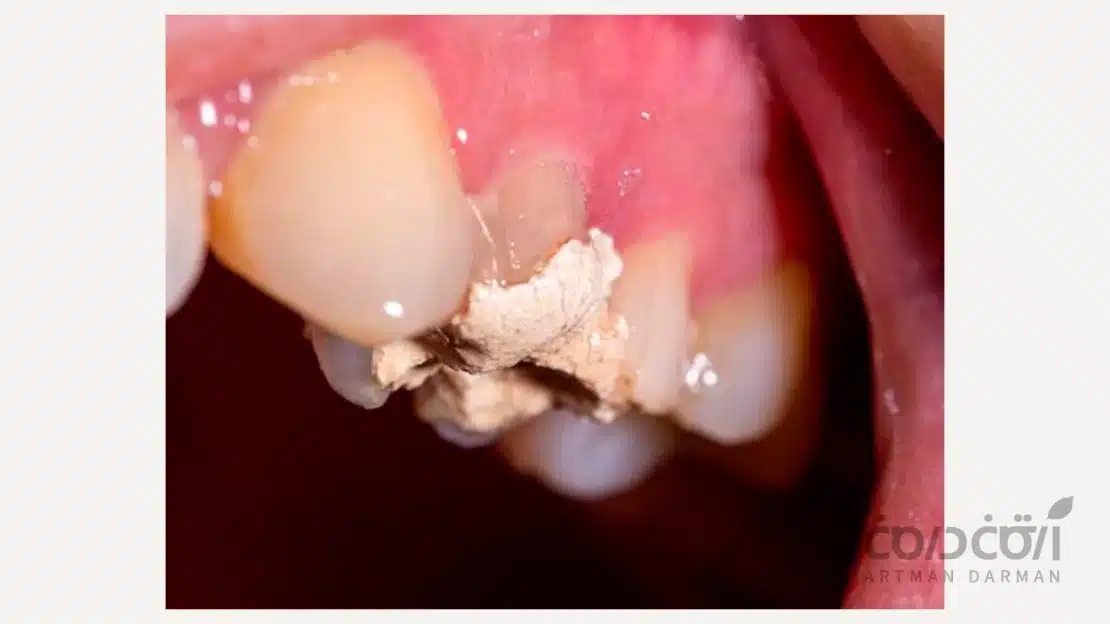

02166003625 09021216575اگر پانسمان دندان عصب کشی شده کنده شود چه اتفاقی می افتد؟

گاهی ممکن است بیمار هنگام خوردن غذا یا مسواک زدن متوجه شود که بخشی از پانسمان جدا شده است. در چنین شرایطی اولین مساله، جلوگیری از ورود مواد غذایی به داخل کانال های درمان شده است. زیرا در نبود یک لایه محافظ، آلودگی محیط دهان می تواند خیلی سریع باعث تحریک بافت ها و ایجاد التهاب شود.